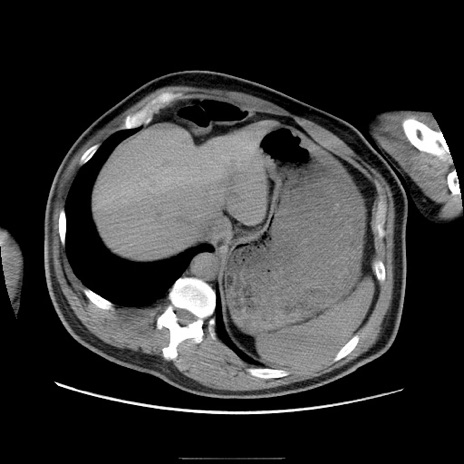

症例

冠状断像